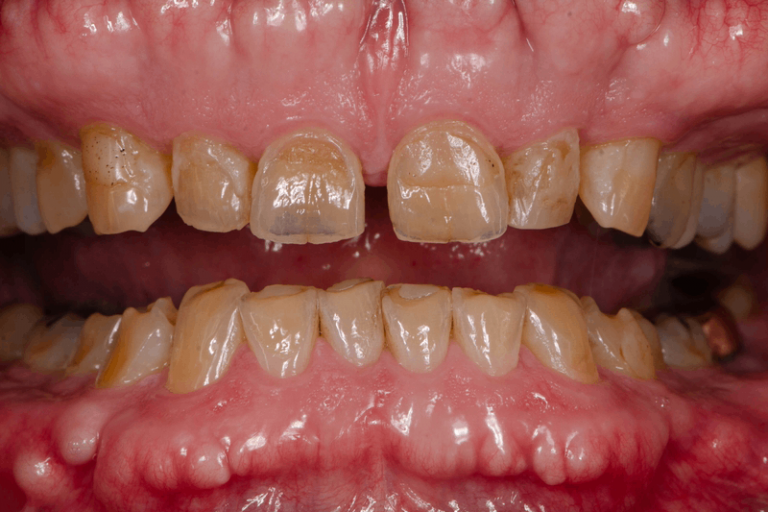

病患初期僅侵蝕琺瑯質時,可以沒有明顯的症狀,只有如牙齒帶黃色、牙齒表層有磨損現象、牙齒邊有破裂、牙齒看來「薄」了等。但當侵蝕到象牙質時,患者會感到牙齒酸軟。此外,在進食冷、熱甜點或酸性食物及飲品;刷牙或使用牙線時會感到刺痛。由於牙齒酸蝕症是慢性的,直到出現遇冷、熱、酸、甜,牙齒敏感症狀出現才會引起注意,而出現這種情況時,可能已經影響到牙齒的咀嚼功能。而且牙齒酸蝕造成的破壞是無法逆轉的,琺瑯質一旦流失就無法復原或再生。